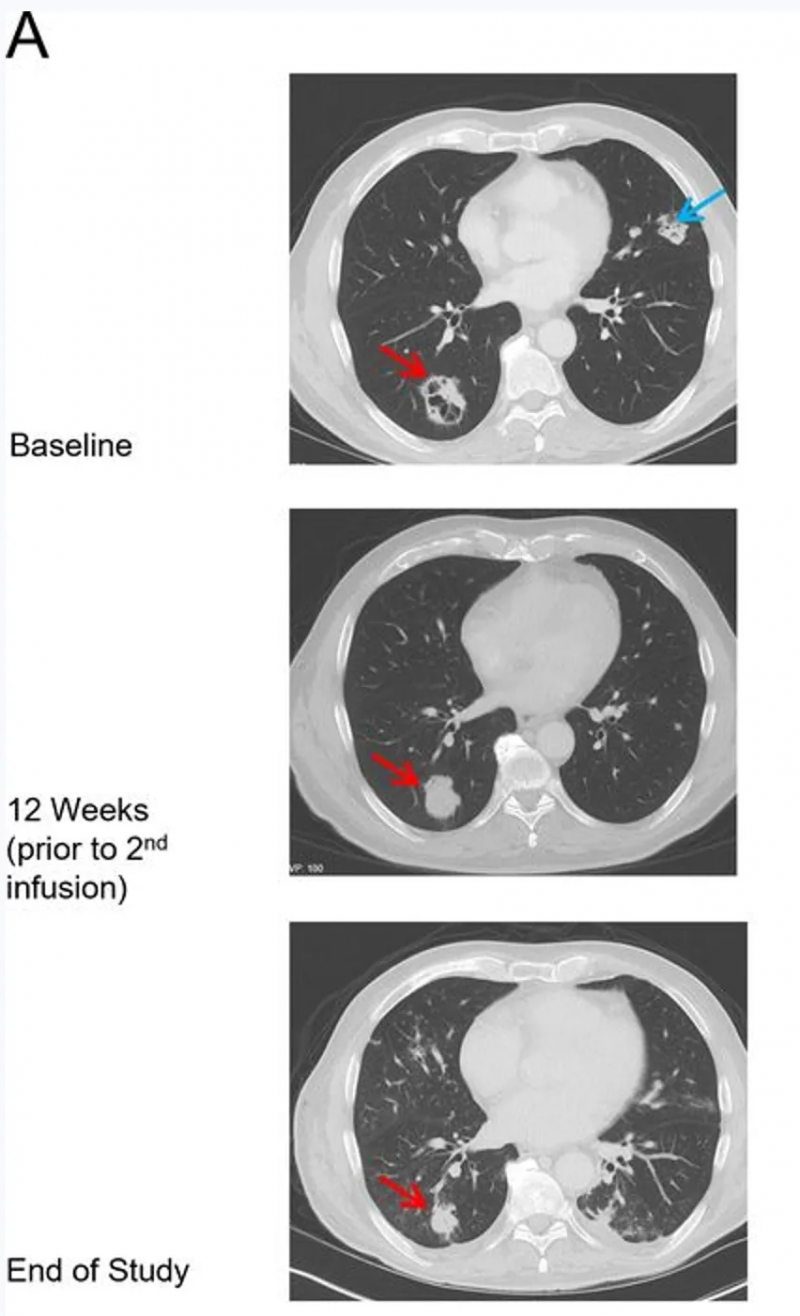

值得关注的是,1例患者(患者9)首次输注后肿瘤较基线缩小25%,后续接受第二次ADP-A2M10输注;第二次输注8周后,该患者按RECISTV.1.1标准达到部分缓解(PR)(图1A、B),且治疗响应期间ADP-A2M10持续存在。下图对比了该患者基线(首次输注前)、第12周(第二次输注前3周)、研究结束时(距首次输注约28周、距第二次输注约13周),其右肺下叶(RLL,红色箭头)与左肺上叶(LUL,蓝色箭头)肿块的CT影像对比(详见下图)。

▲图源“BMJ”,版权归原作者所有,如无意中侵犯了知识产权,请联系我们删除